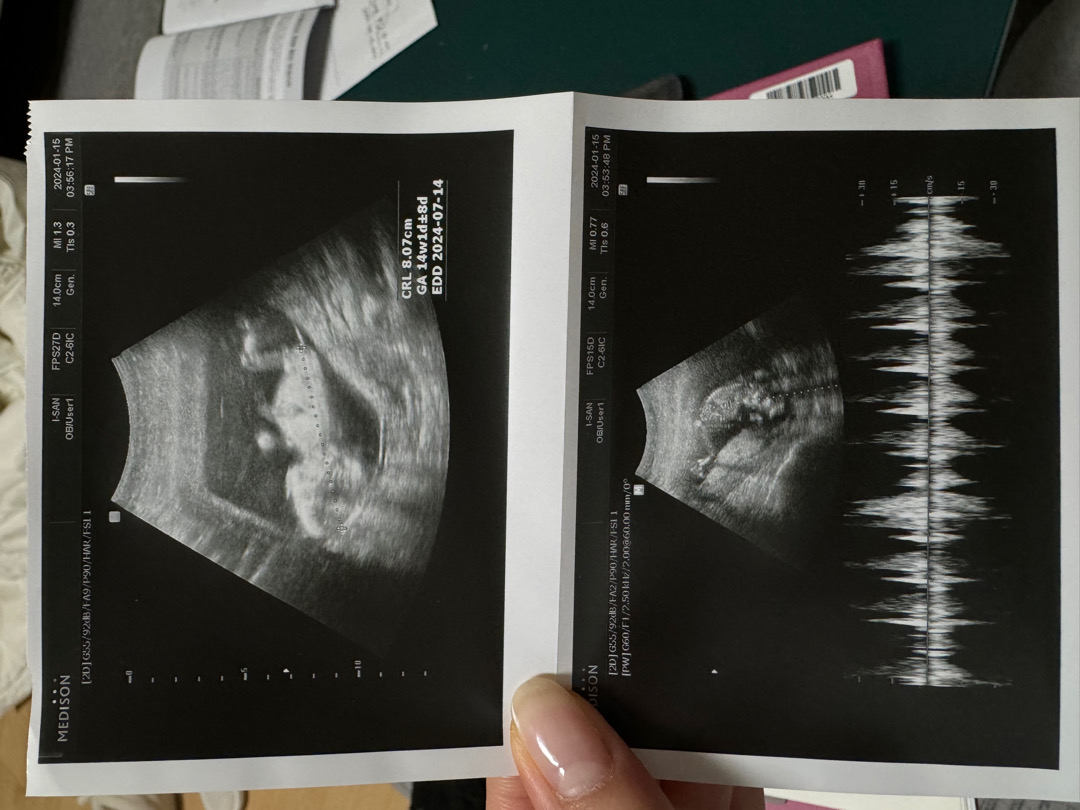

14주 1일차 딸 혹은 아들일까요?

병원에서는 딸일 확률이 좀 더 높다고 하는데 맘님들이 보시기에는 딸일까요, 아들일까요???ㅠㅠ 궁금해요~~~

저도 첫째 14주에 딸이라고 듣고 딸 낳았어요~^^ 생식기와 엉덩이 각도가 평행이면 딸일 확률 높다고 들었어요~!